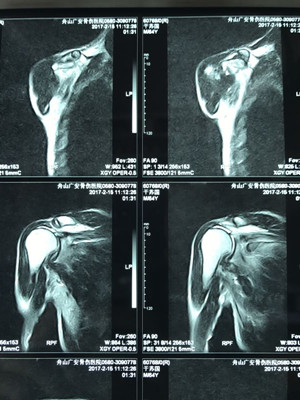

據(jù)了解,干大伯半年前因外傷導(dǎo)致頸椎外傷伴截癱,右肩關(guān)節(jié)脫位伴巨大肩袖斷裂,曾在廣安醫(yī)院接受頸椎手術(shù),術(shù)后恢復(fù)良好。后來,干大伯要求進(jìn)一步對肩關(guān)節(jié)進(jìn)行治療。廣安醫(yī)院副院長危立軍及運(yùn)動(dòng)醫(yī)學(xué)科主任羅軍對其進(jìn)行詳細(xì)檢查后,認(rèn)為干大伯的右肩存在巨大不可修復(fù)肩袖撕裂伴嚴(yán)重的關(guān)節(jié)炎,肩袖的脂肪浸潤達(dá)到四級,治療上有一定的挑戰(zhàn)性,只能通過特殊類型的人工肩關(guān)節(jié)——反式全肩人工關(guān)節(jié)來重建關(guān)節(jié)功能。